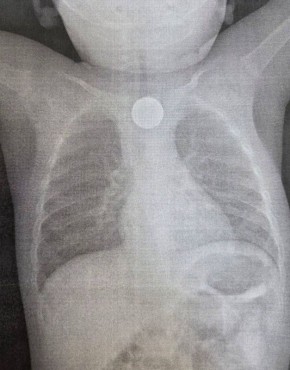

В Улан-Удэ медики спасли жизнь ребенку. Повод для обращения шокировал даже опытных врачей: годовалый мальчик проглотил сразу два опасных предмета - монету и литиевую батарейку.

- Бригада врачей во главе с эндоскопистом Зориком Хангаловым немедленно провела операцию. С помощью эндоскопа они извлекли из пищевода малыша двухрублевую монету и маленькую, но очень опасную литиевую батарейку. Именно она, вступив в реакцию со слизистой оболочкой, успела вызвать сильный химический ожог, - рассказали в пресс-службе ДРКБ.